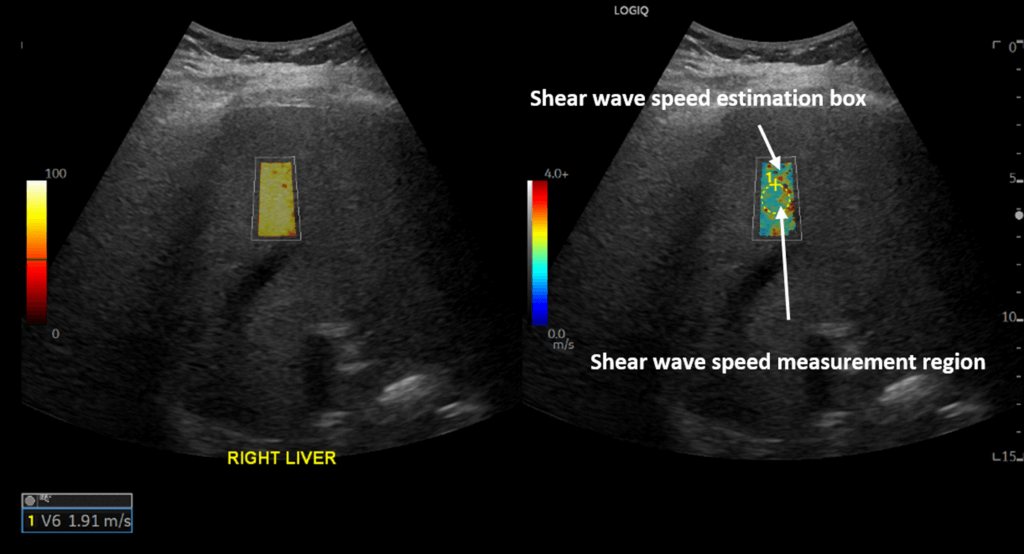

Researchers compared patients who had COVID-19 with two control groups, and each received an ultrasound shear wave elastography. The assessment measures how stiff tissue is.

COVID-positive patients had a high median liver stiffness of 7.68 kPa, compared to 5.99 kPa stiffness in those who didn’t have the ailment. Patients were organized into one of three groups, based on whether they received elastography and whether they tested positive.